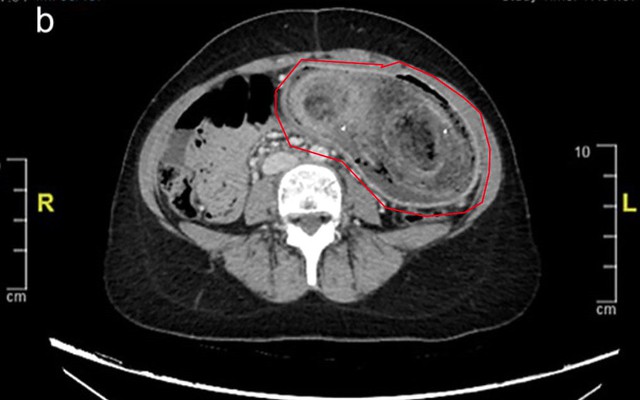

Trong khi tất cả các xét nghiệm trong phòng thí nghiệm đều bình thường, kết quả chụp CT xác nhận rằng búi tóc khổng lồ đã kéo dài từ dạ dày đến tá tràng.

Do kích thước của khối tóc, việc loại bỏ bằng phương pháp nội soi là không thể nên nữ bệnh nhân đã phải trải qua phẫu thuật mở dưới gây mê toàn thân.